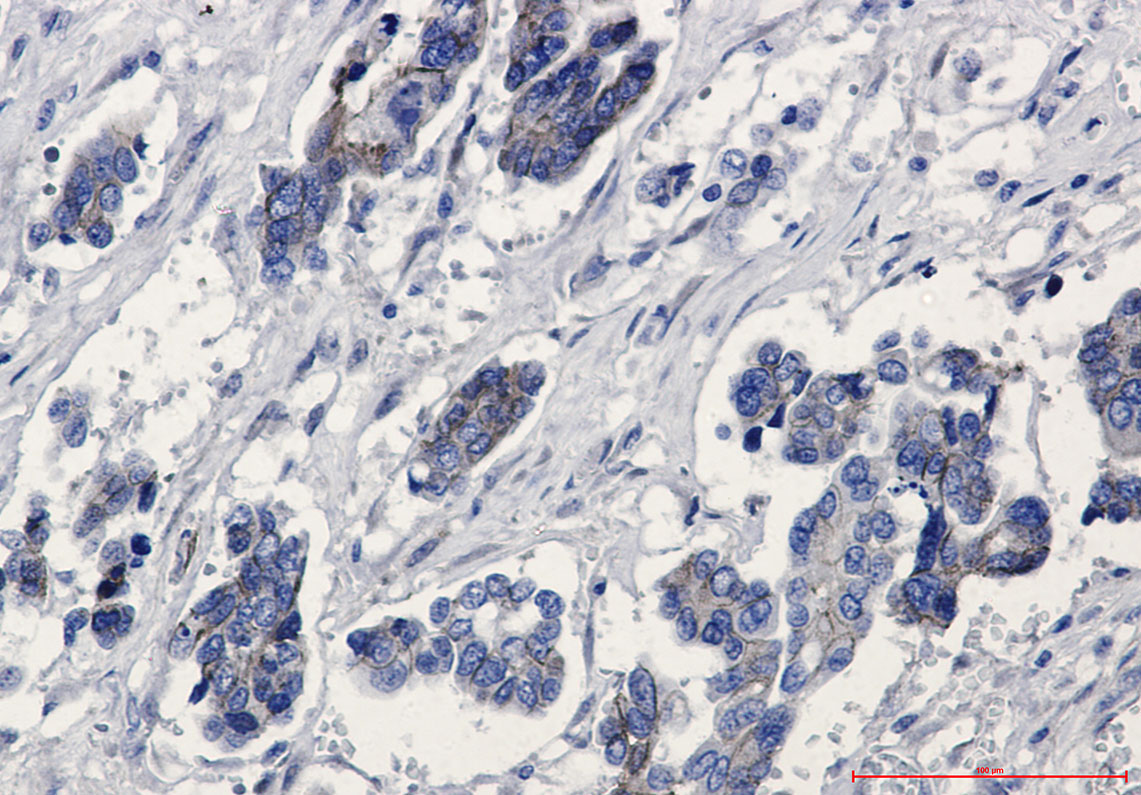

- Immunohistochemistry analysis of paraffin-embedded Human Cholangiocarcinoma using beta Catenin antibody. High-pressure and temperature Sodium Citrate pH 6.0 was used for antigen retrieval.